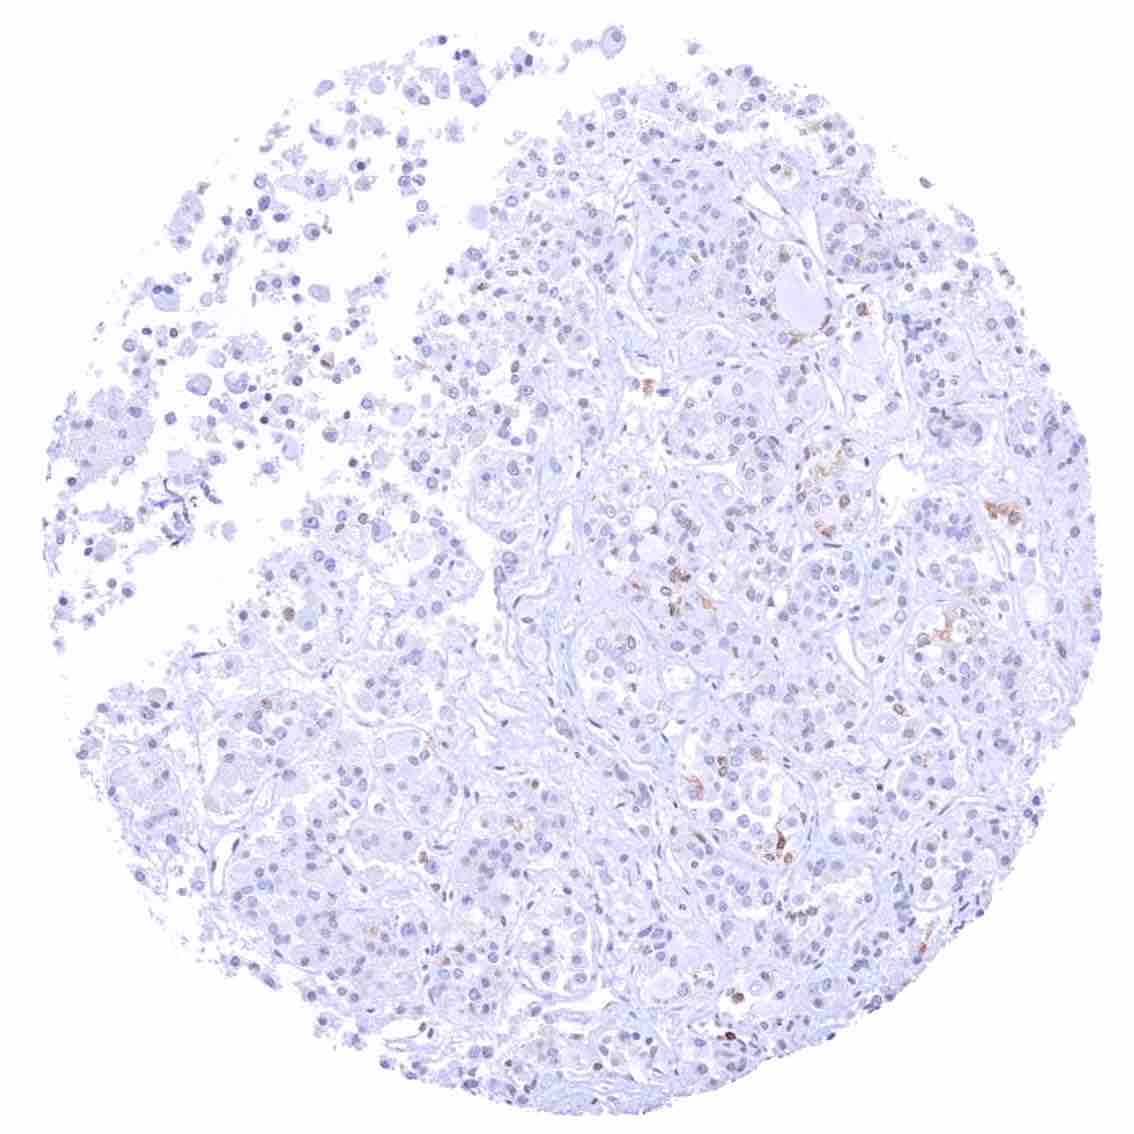

Lymph node – Strong bcl-2 positivity of a large fraction of lymphocytic cells in the interfollicular area and around germinal centres while almost all cells in germinal centres are bcl-2 negative.